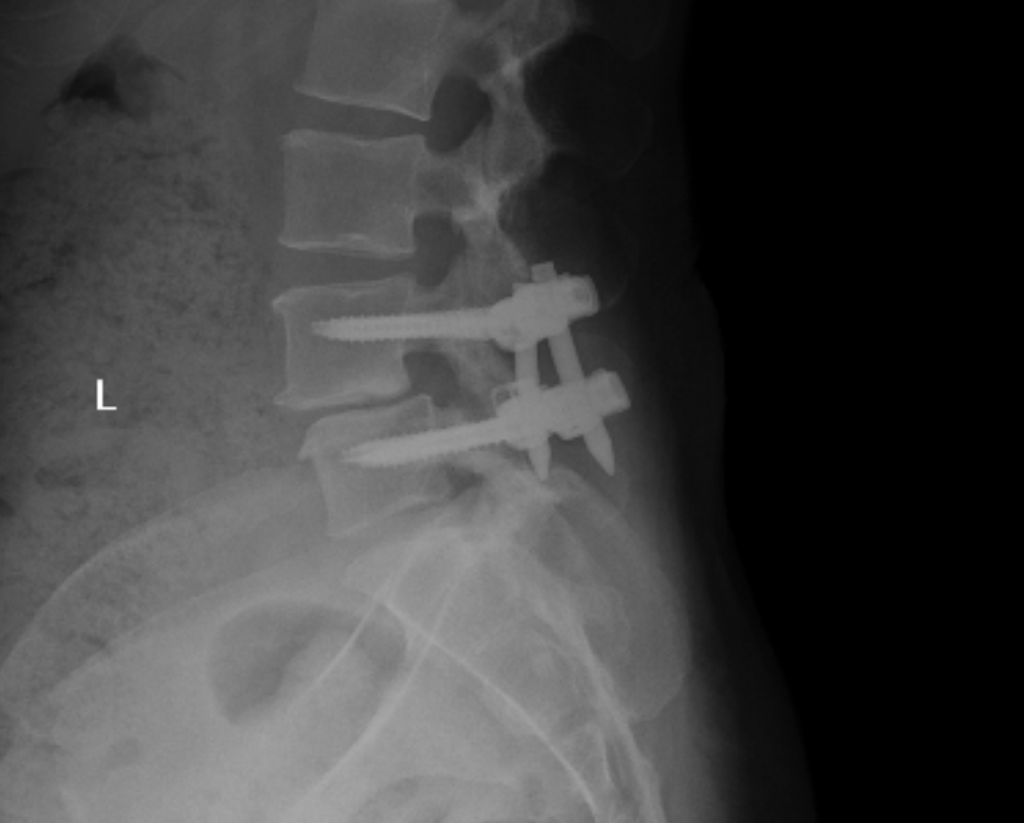

Spinal Stenosis

I’ve always been active. I’ve done everything - boxing, Pilates, barre, and in my mid-40s after Covid I started to run and ran two half marathons in 2022 and 2023. I first started to experience pain in my hip and down my right leg during my first pregnancy. The leg pain subsided but the hip pain never did. When I took up running, that’s when things went downhill. First the plantar fasciitis, then the constant leg pain like I had pulled a hamstring. Dr. Baxi at first used cortisone on both my foot and back. Then we did shockwave therapy on my foot which helped tremendously. But after a second epidural on my back didn’t work I knew it was time for surgery. Dr. Dowdell was great. It was tough at first and he assured me after six months I could get back to my former life. Now I’m back to boxing and I’m hoping to start training for and run in the NYC marathon this Fall.

James E. Dowdell III, MD

Spine Surgeon